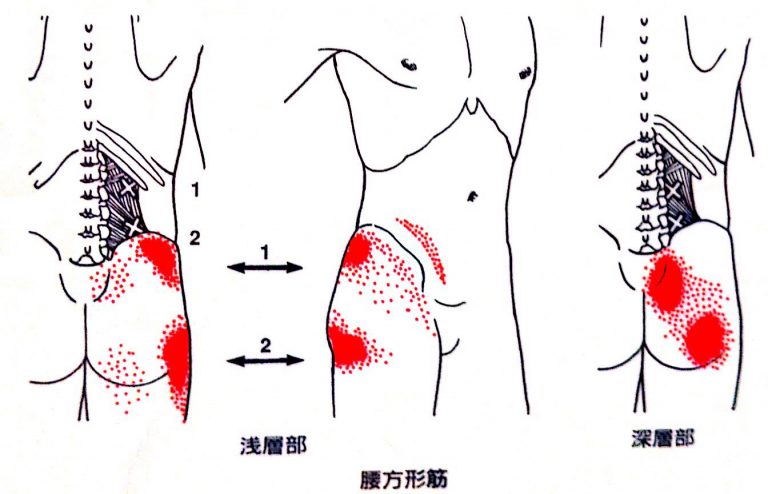

2.腰方形筋による腕のだるさ・しびれ

腰方形筋は、腰の深い位置にある筋肉で、骨盤や腰椎のバランスを保つためにとても重要な役割を担っています。

姿勢のゆがみにも大きく関わる筋肉です。

この腰方形筋に トリガーポイント(×印の部分) ができて固まると、神経を刺激し、次のような痛みが広がることがあります。

- お尻の横の痛み

- 太ももの外側の張りやしびれ

- 足の側面にかけての違和感

赤い範囲のように、脚の外側へ放散するタイプの坐骨神経痛で、「歩くと横に痛みが走る」「長時間立つと足の側面がしびれる」などの訴えが多く見られます。

腰方形筋が硬くなると骨盤の傾きにも影響し、坐骨神経痛を悪化させる原因になるため、的確なケアが必要です。